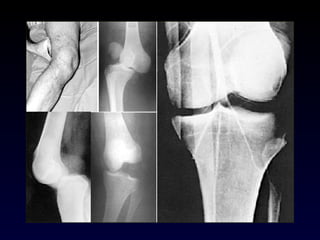

Fx rótula

Patela bipartita